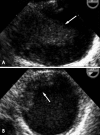

Pedunculated thrombus in the aortic arch that is associated with cerebral infarction is very rare requires prompt diagnosis and treatment to prevent occurrence of another devastating complication. Transesophageal echocardiography is useful for detecting source of embolism including aortic thrombi. The treatment options of aortic thrombi involves anticoagulation, thrombolysis, thromboaspiration, and thrombectomy. Here we report a case of huge thrombus in the aortic arch, resulting in acute multifocal cerebellar embolic infarct in patient without any risk factors for vascular thrombosis. Thrombi in the aortic arch were diagnosed by transesophageal echocardiography and treated with anticoagulants successfully.